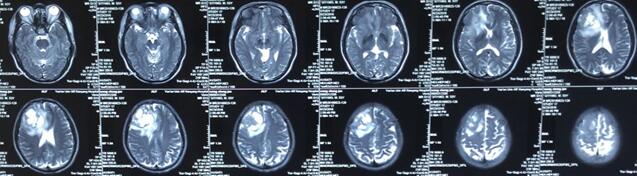

患者王某某,男,53歲,因“間斷頭痛半月”入神經內科十二病區,發現顱內占位后轉入神經外科。既往患者有肺Ca病史,于一年前行手術治療。頭顱影像學診斷膠質瘤?轉移瘤待排。2016年6月29日在3.0T磁共振定位后,劉增強副主任與其團隊為患者實施了立體定向腦內病變活檢術,此患者病灶為囊實性,手術難度較大,而一旦囊液流失則會發生腦組織漂移,導致靶點移位,因此手術計劃制定尤為重要,入顱點為右額部,穿刺后首先達到腫瘤實性部分,獲取病灶標本后,抽出部分囊液以緩解患者高顱壓癥狀,經過精細的手術操作,最終成功獲取腫瘤標本,并且抽出約20ml腫瘤液,患者情況穩定,術后兩小時即下床活動。

術后冰凍切片報告考慮轉移瘤,我院石蠟病理結果為少許低分化癌組織,結合病史符合肺癌腦轉移。